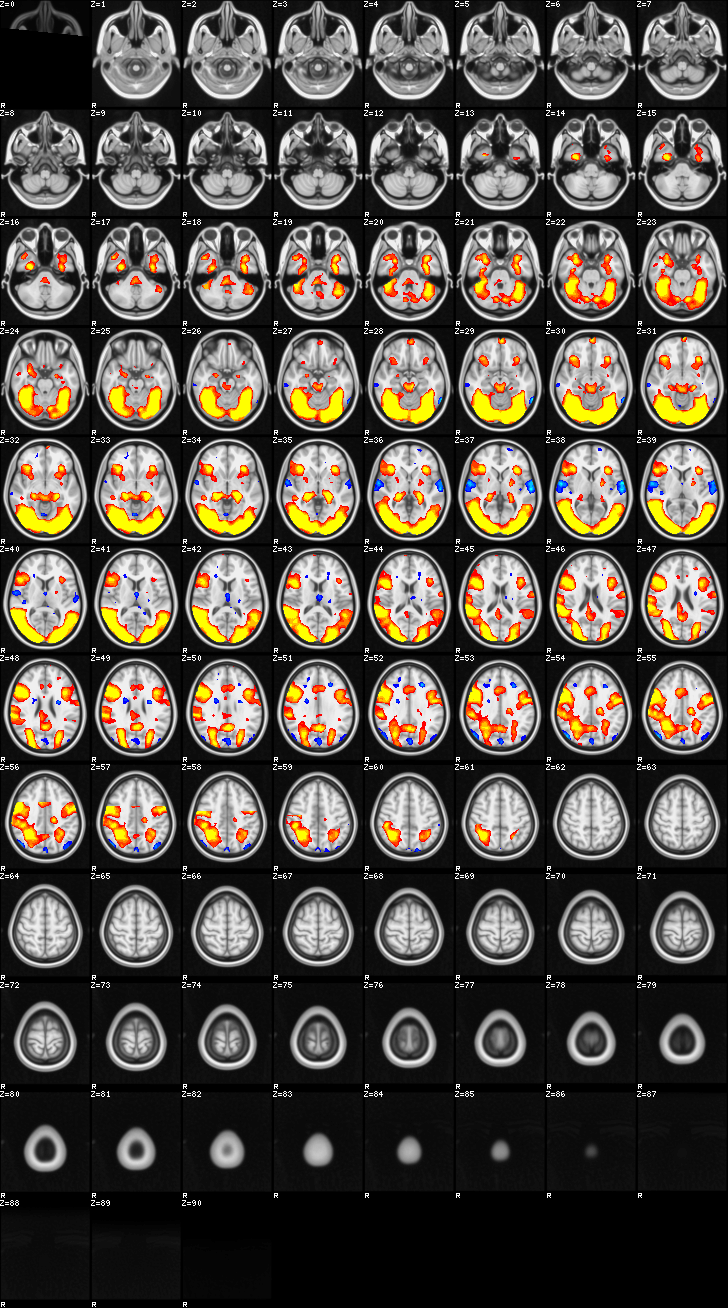

Mixed Effect (flame1)¶

ATM it is 26 subjects, 8 mm FWHM spatial (simple gaussian) smoothing, preliminary results only

Images thresholded abs value > 2.3 and colormap goes from 2.3 to 5 (red->yellow) or -2.3 to -5 (blue->lightblue)

00-FgtC¶

01-FltC¶

02-MOTOR¶

03-self¶

04-friend1¶

05-friend2¶

06-friend3¶

07-friend4¶

08-control1¶

09-control2¶

10-control3¶

11-control4¶

12-Face¶

13-F¶

14-C¶